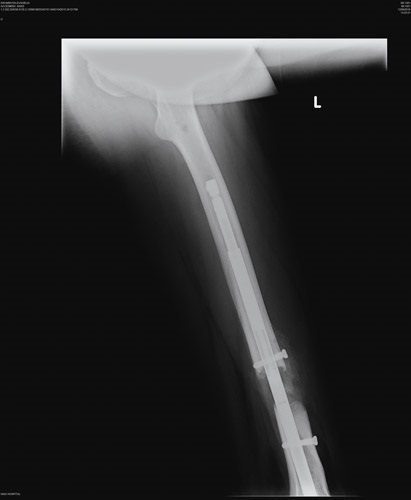

Το PRECICE® εμφυτεύεται χειρουργικά σε ένα ή περισσότερα οστά του κάτω άκρου (μηριαίο οστό ή κνήμη). Η επιμήκυνση (φωτογραφία 1) λαμβάνει χώρα όταν ο ιατρός ενεργοποιεί με μη επεμβατικό τρόπο τη μονάδα απομακρυσμένου ελέγχου που βρίσκεται ακριβώς επάνω στο εμφύτευμα. Το εσωτερικό εμφύτευμα χρησιμοποιεί τεχνολογία μαγνητών για την επιμήκυνση του οστού του άκρου μέσω μη επεμβατικού συστήματος απομακρυσμένου ελέγχου, το οποίο ρυθμίζει το εμφύτευμα εξωσωματικά.

Το εμφύτευμα PRECICE® κρατά τα οστά ενωμένα, έως ότου ο οργανισμός δημιουργήσει νέο οστό για την κάλυψη του κενού. Κατά τη φάση της σταθεροποίησης, το οστό αποκαθίσταται. Αφαιρείται από το μηριαίο οστό ή την κνήμη μετά το σχηματισμό ώριμου οστού (ο οποίος λαμβάνει χώρα συνήθως εντός 12 μηνών από την αρχική εμφύτευση) και την επίτευξη του επιθυμητού μήκους του άκρου